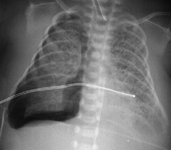

Malformação congênita da via aérea pulmonar (CPAM; antes conhecida como malformação adenomatoide cística congênita [MACC])

Do acervo de Ponthenkandath Sasidharan, MD; usado com permissão